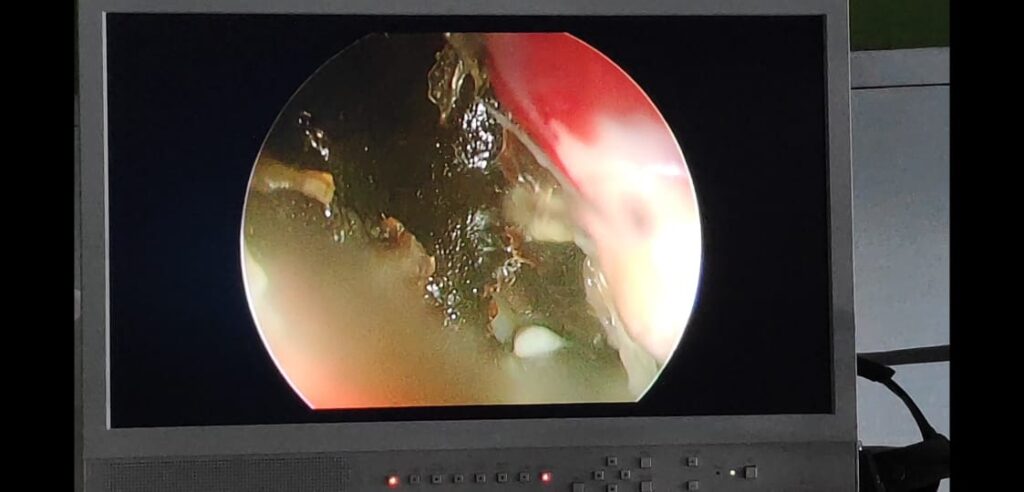

During the surgery, mucormycosis was found to involve the right maxillary sinus, ethmoid sinuses, middle and inferior turbinates, posterior part of the nasal septum. Sphenoid sinus was found to be oedematous but clear of gross disease.

The lamina papyracea (thin wall separating orbit and nasal cavity) and floor of the brain was found to be intact. All parts involved in the mucormycosis were cleared of the disease. The patient is stable after the surgery.